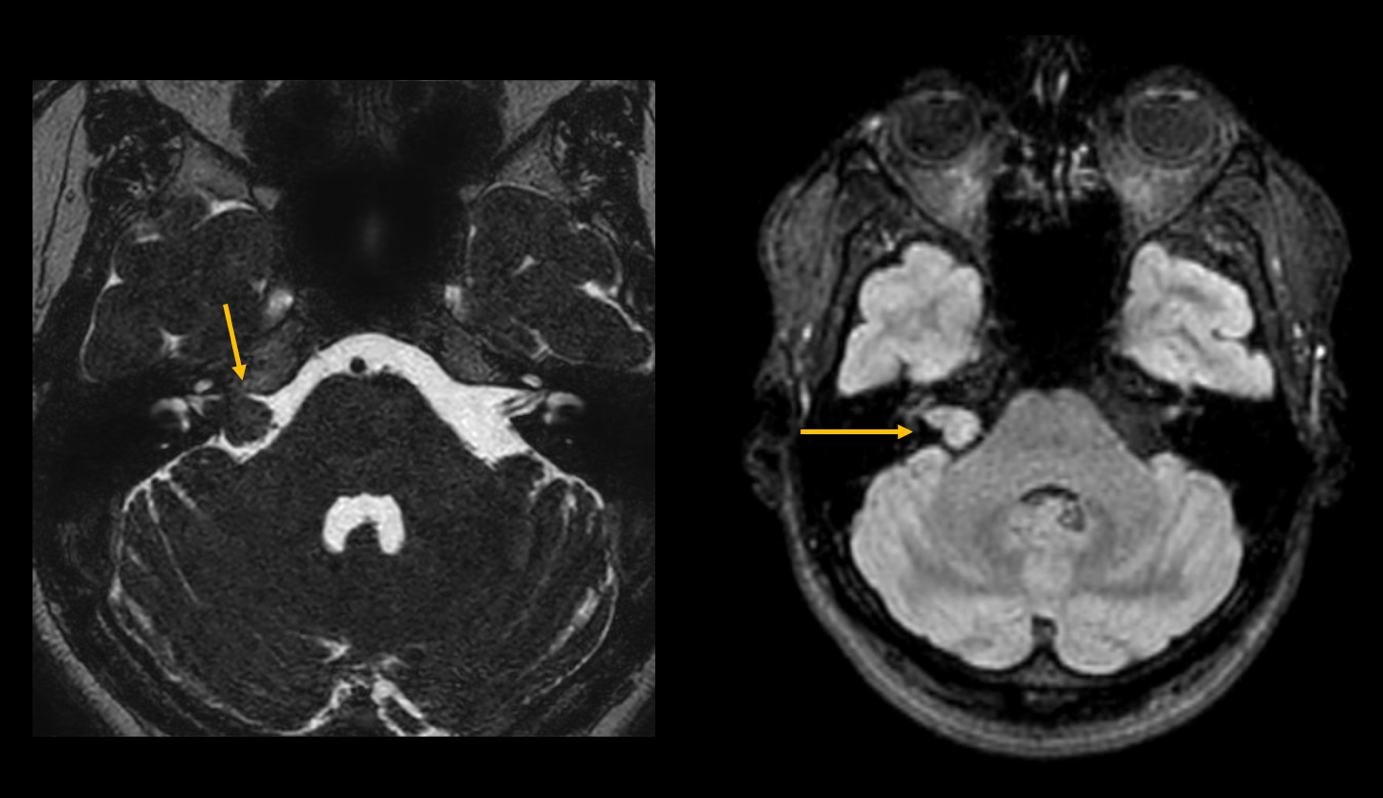

L'acufene non è inizialmente una malattia a sé stante, ma un sintomo di vari disturbi. All'inizio, spesso sono presenti danni e malattie nell'orecchio stesso, ad esempio a causa di un'infiammazione o di una forte esposizione al rumore. Se i sintomi peggiorano, è consigliabile sottoporsi a una risonanza magnetica (RM). A una paziente di 47 anni (vedi foto) è stato diagnosticato un neurinoma acustico sul lato destro, con conseguente perdita dell'udito.

image2.png

Figura 2: RM della fossa posteriore con ponderazione T2 e T1. Mostra una massa isointensa in T2-W nel meato acustico interno, coerente con un neurinoma acustico.